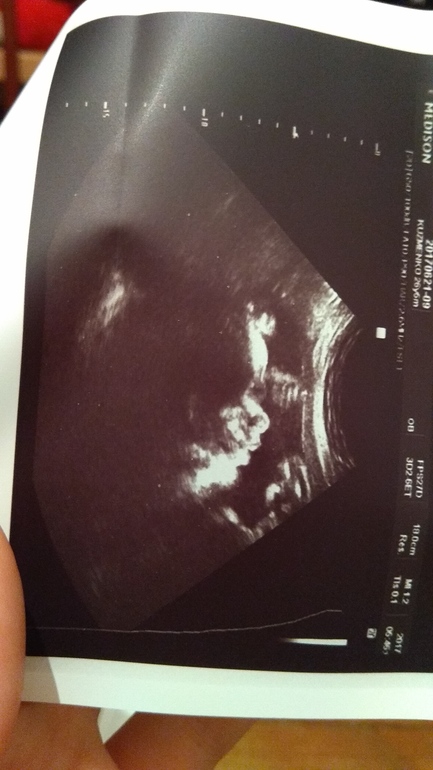

Всё у нас хорошенько, как опережали, так и продолжаем в том же духе. Головастик у нас растет и на попе спокойненько сидит, но после утренних попыток выбраться с меня через мой бок я не удивлена, что перевернулся на попу

Божечки, какой он сладкий присладки, перед узи я сьела мароженку, а он так причмокивал и язычок высовывал, наверное ему тоже понравилось

. Во время узи с врачом и поговорили, и посмеялись, дала пару фоток, делюсь с вами, ну и параметры на память